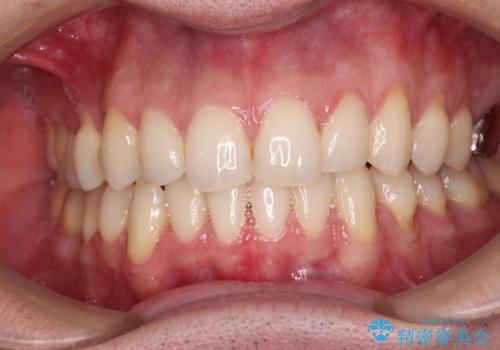

ディープバイトと叢生 インビザラインによる矯正治療

- 前歯のディープバイトと叢生を気にして来院された患者様です。

目立ちにくい装置を希望されていたため、ワイヤー装置とインビザラインを提案したところ、インビザラインを希望されました。

上下ともに叢生が認められたため、親知らずすべてを抜歯し、歯列全体を後方へ移動させることで歯列を整えることとしました。

ディープバイトもデコボコも改善され、気になっていた銀歯もセラミックとなり、患者様には大変満足していただきました。